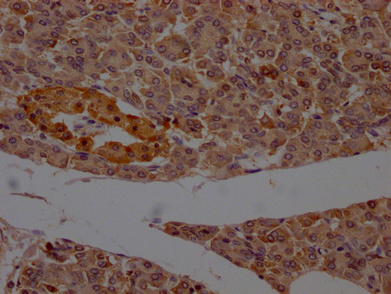

IHC image of CSB-PA017627LA11HU diluted at 1:200 and staining in paraffin-embedded human pancreatic tissue performed on a Leica BondTM system. After dewaxing and hydration, antigen retrieval was mediated by high pressure in a citrate buffer (pH 6.0). Section was blocked with 10% normal goat serum 30min at RT. Then primary antibody (1% BSA) was incubated at 4°C overnight. The primary is detected by a Goat anti-rabbit polymer IgG labeled by HRP and visualized using 0.05% DAB.

推薦稀釋比:Application Recommended Dilution IHC 1:200-1:500